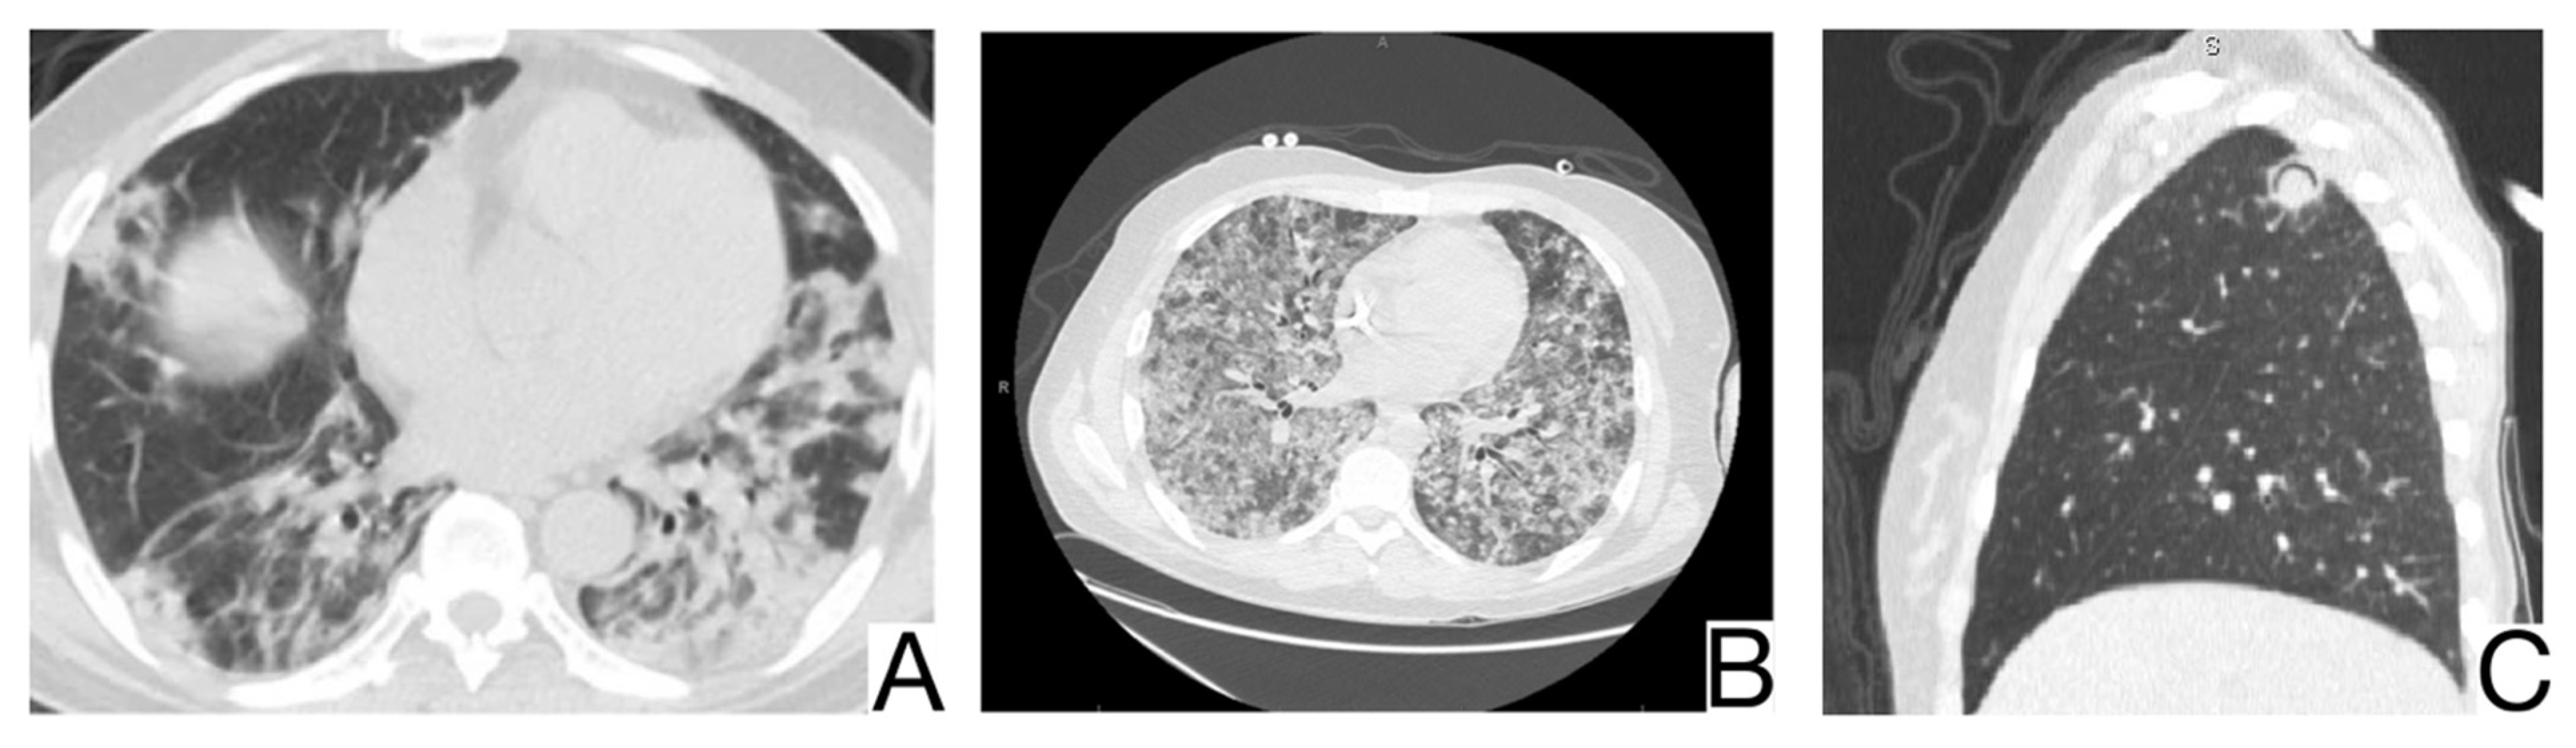

10.8. Eosinophilic Pneumonia

Eosinophilic pneumonia represents a distinct group of pulmonary diseases accompanied by peripheral eosinophilia. Laboratory tests and history are crucial for a correct differential diagnosis. HRTC is essential for positive and differential diagnosis [].

Imaging characteristics for differential diagnosis are (Figure 10A,B): the absence of the cobblestone in simple pulmonary eosinophilia (SPE), also known as Loeffler syndrome); pleural effusions, centrilobular nodules, and thickening of lar bundles in acute eosinophilic pneumonia []; centrolobular consolidations with occasional frosted glass and cobblestone opacities in chronic eosinophilic pneumonia; additional findings in chronic eosinophilic pneumonia are represented by nodules, atelectasis, band opacities, and pleural effusions [,].

Figure 10. Chronic eosinophilic pneumonia (A,B). Consolidation throughout both lungs. Note. Case courtesy of Dr. Henry Knipe, Radiopaedia.org, rID: 39331.

10.10. Pulmonary Alveolar Proteinosis

Pulmonary alveolar proteinosis-PAP is a syndrome caused by an accumulation of surfactant in the pulmonary alveoli. It can be primary in most cases or secondary to toxic inhalation syndromes, hematological neoplasms, and immune deficiency. History, laboratory tests, and comparison with previous HRCT are helpful [,].

CT differential diagnosis is highlighted by (Figure 12A,B): mainly centro-parenchymal and perihilar cobblestone areas; the juxtaposition of severely affected secondary lobules and normal secondary lobules [,]; rarely, condensations with air bronchogram in severe forms; progressive fibrotic changes; pleural effusions, cardiomegaly, and lymphadenopathy, which are characteristics of complicated PAP [].

Figure 12. Pulmonary alveolar proteinosis (A,B). Bilateral areas of crazy paving. Note. Case courtesy of Dr. Adrià Roset Altadill, Radiopaedia.org, rID: 74896.